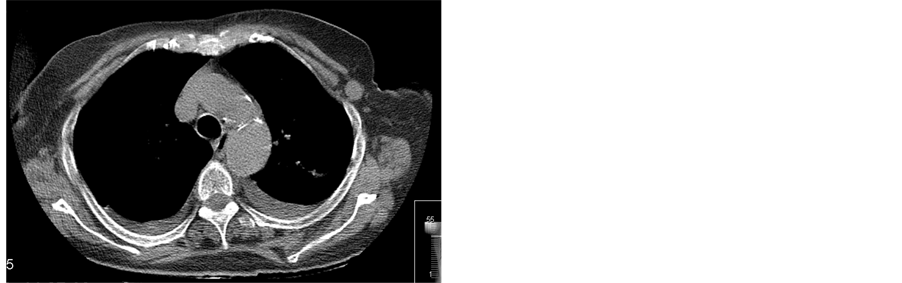

Staging of the tumor was completed with a thorax CT scan that identified an enlarged lymph node in the left axilla with 15 mm in diameter. There were no lung metastasis nor mediastinicenlarged lymph nodes (Figure 2(a) and Figure 2(b)).

Figure 2. (a) Thorax CT scan showing an enlarged lymph node in the left axilla (arrow); (b) Thorax CT scan showing an enlarged lymph node in the left axilla (arrow).